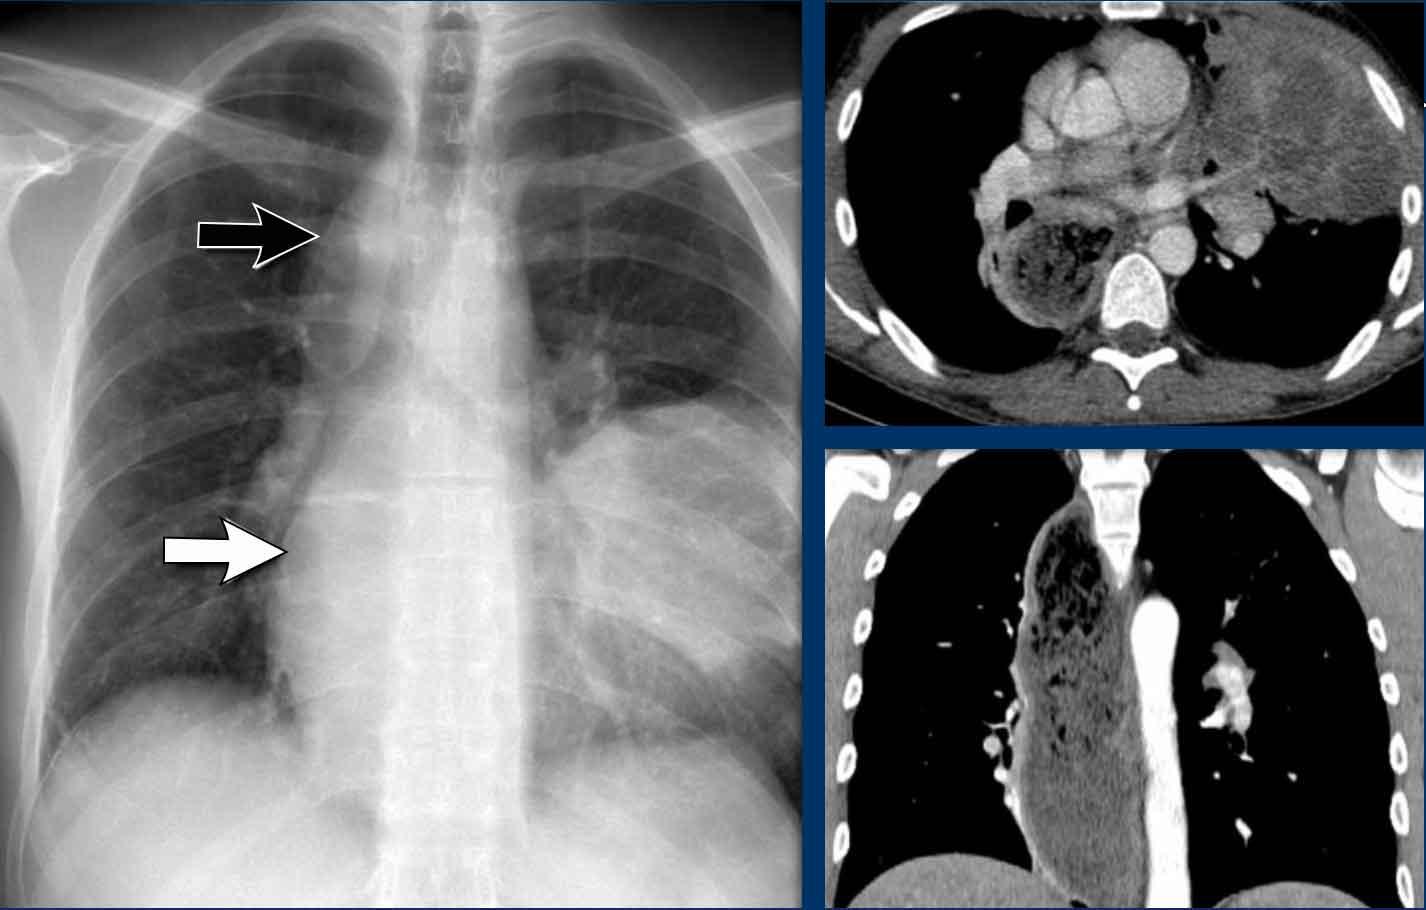

Dịch chuyển đường azygô-thực quản (2) – Hạch to dưới carina

Một nguyên nhân thường gặp gây dịch chuyển đường azygô-thực quản là hạch to dưới carina (trạm 7).

Trên phim X-quang ngực, lưu ý hình ảnh đường azygô-thực quản bị đẩy lên trên ngay dưới carina, phù hợp với hình ảnh hạch bạch huyết dưới carina to (mũi tên đen).

Ngoài ra còn thấy hạch to cạnh khí quản phải, đẩy dải cạnh khí quản phải (mũi tên trắng) và làm lệch khí quản sang trái.

Tiếp tục với hình ảnh PET-CT…

Hình ảnh PET

- PET-CT cho thấy hình ảnh hạch to tăng chuyển hóa lan rộng ở trung thất và vùng cổ, rõ ràng hơn so với trên phim X-quang ngực.

Tiếp tục với hình ảnh CT và siêu âm…

Hình ảnh CT

- CT có thuốc cản quang cho thấy hạch to dưới carina kích thước lớn, đẩy lệch ngách azygô-thực quản và chèn ép nhĩ trái.

- Sinh thiết hạch vùng cổ xác nhận ung thư phổi tế bào nhỏ.